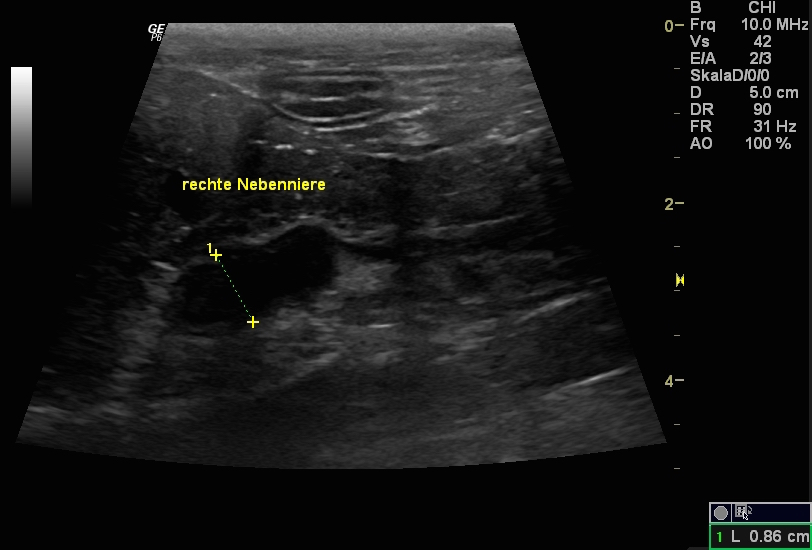

Im Rahmen einer Ultraschall-Untersuchung der Bauchorgane fiel eine stark vergrößerte Leber auf. Die Nebennieren wiesen grenzwertig große Durchmesser auf (Abb. 2, Abb. 3).